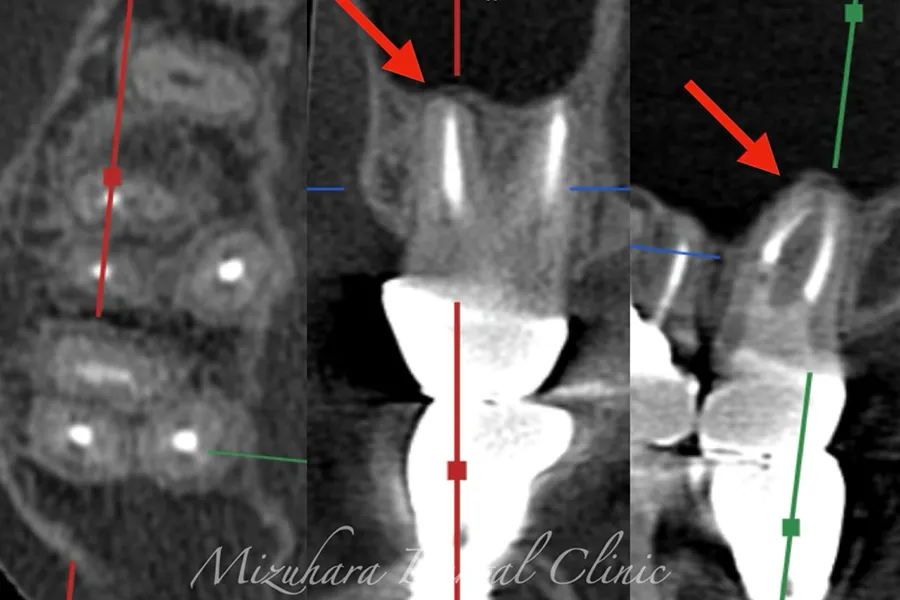

予知性の高い治療を提供できるだけ患者様の大切な歯を残し、10年、20年先まで健康な状態を保てるよう、長期的な視点で治療を計画します。そのために最も重要なのが、「診査」と「診断」です。的確な診断は精密な診査から生まれ、治療結果を大きく左右します。問診や簡易検査だけでは見逃されがちな病変も、CTやマイクロスコープなどの最新の医療機器を活用し、時間をかけて丁寧に「診査・診断」を行います。

世界基準の成功率を目指した精密根管治療

根管治療

当院では豊マイクロスコープ、ラバーダムを使用し、世界基準の成功率を目指した精密根管治療による「歯を残す」ための治療をご提供します。